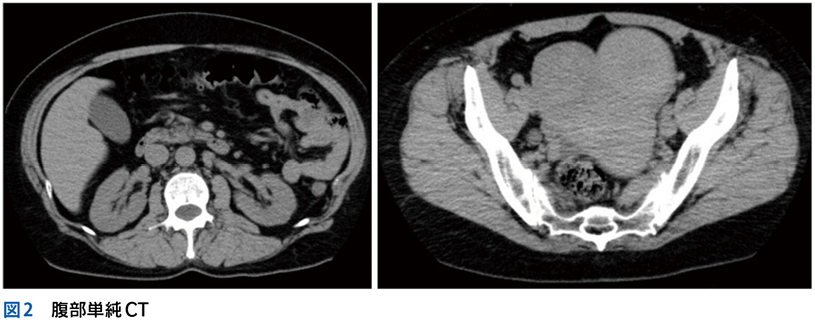

▶ 最後に,SQについて大切な点を補足しておく。それは「〇〇がない」という陰性情報も重要なSQとなりうる,ということだ。診断に関連する(鑑別に挙がっている疾患の確率を上げ下げする)陰性情報をpertinent negativesと言うが,これは時に陽性情報(「〇〇がある」)と同等,あるいはそれ以上に重要となることがある。「突然発症した腹膜刺激徴候のない重度の腹痛」「局所症状のない遷延性発熱」「単純CTで尿路結石がみられない突然の片側側腹部痛」のように,意味のある陰性情報をSQとして用いることで鑑別のフレームをぐっと狭めることができる。SQによる修飾の際には,こういったpertinent negativesも意識しておきたい。